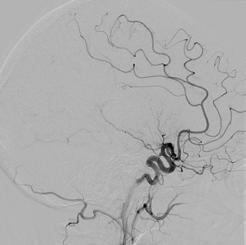

I mages from the embolectomy procedure performed on the patient whose CT perfusion image is on the cover. Both the “before” and “after” are lateral projections with the x-ray camera positioned over the patient’s head.

The “before” image has a paucity of blood vessels because there is a blood clot in the middle cerebral artery that is occluding flow into all of the branches from the middle cerebral artery. The “after” image was obtained after the embolectomy procedure was performed to remove the blood clot in the middle cerebral artery. This shows restoration of normal blood flow to the brain.

Comparing the “before” and “after” images shows the very large number of blood vessels, and subsequent area of the brain, that were at risk of causing permanent stroke for the patient. Thankfully, the blood vessels were able to be reopened in time and the patient made a full recovery.

BEFORE AFTER